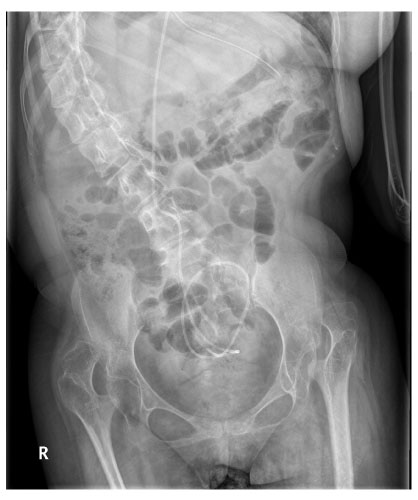

Fig. 1

Simple abdominal X-ray film shows severe kyphosis and ventriculo-peritoneal shunt catheter in the abdomen. Normal intestinal gas pattern is seen.

Fig. 1 Simple abdominal X-ray film shows severe kyphosis and ventriculo-peritoneal shunt catheter in the abdomen. Normal intestinal gas pattern is seen.